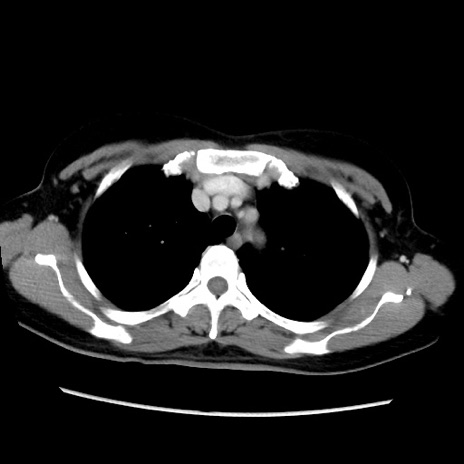

症例39(横断像)

【症例】40歳代女性

【主訴】上下腹部痛

【現病歴】2日目から下腹部痛あり。夜間は痛みで眠れなかった。昨日より上腹部痛と下痢が出現。臥位で痛みは軽快したため、休んでいた。本日になって臥位でも立位でも痛みが強くなってきたため救急要請。

【既往歴】子宮内膜症

【身体所見】部:平坦・軟、左上下腹部に圧痛あり、反跳痛あり。

【データ】WBC 21800、CRP 26.78